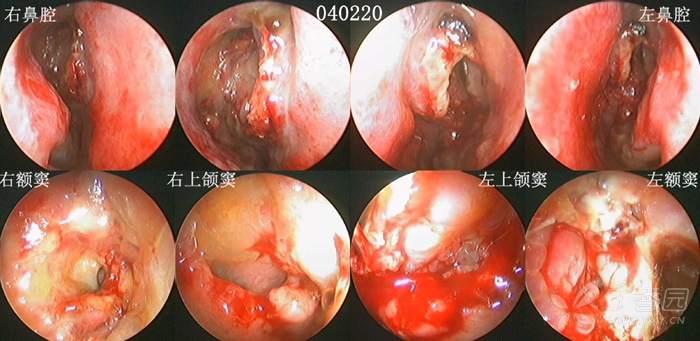

病例2:2004年2月12日手术,从手术创面的广泛性,到术后随访的频繁性,同样非常严重,站在今天鼻-鼻窦剔骨法成形术的角度,对于这样的做法和结果,既无法理解,更难以接受(见下图及图中的时间标示)。

首先,术后3-7天开始清理,之后每1-2周复诊一次,给予鼻内镜检查、清理,以及术后囊泡样变、炎症迁延、术腔粘连、窦口狭窄,对于绝大多数的患者而言,几乎就是一种常态。但频繁的内镜随访给患者带来的心理、经济、时间等各种压力,也使能够长期坚持随访者占比极少。因此,术后随访治疗能够坚持到完成粘膜上皮化的占比率,也受到了极大影响。